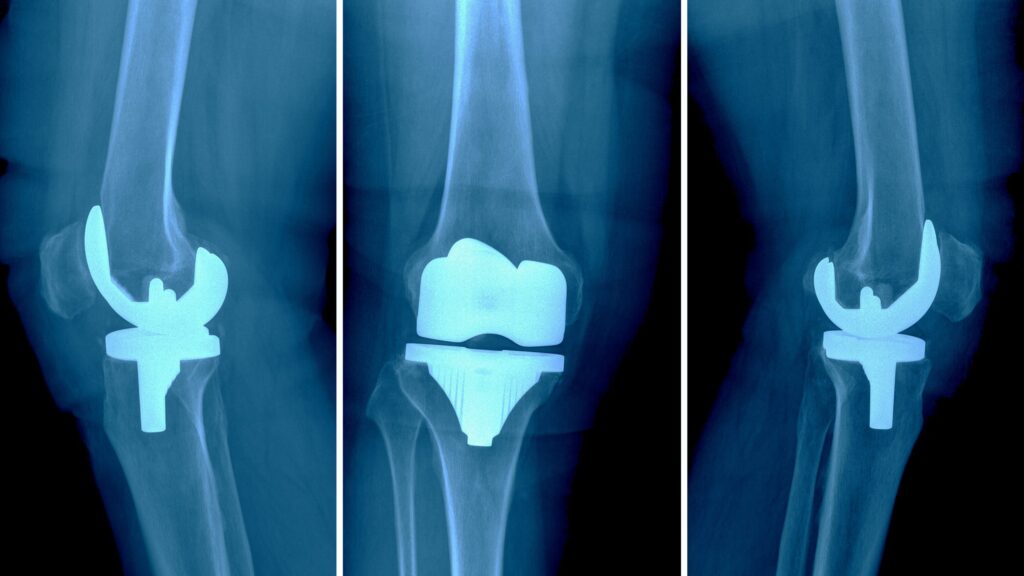

While knee replacement surgery is often successful in reducing pain and improving mobility for individuals with advanced knee arthritis or joint damage, some patients may experience complications or ongoing discomfort after the procedure. A painful or failed knee replacement refers to cases where the surgery does not achieve the expected outcomes, leading to persistent pain, stiffness, or instability. Identifying the underlying cause is essential for determining the most appropriate treatment to restore function and improve quality of life.

A painful or failed knee replacement occurs when the results of a total or partial knee replacement surgery are not satisfactory. This may involve ongoing pain, stiffness, instability, or a failure of the implant to function as intended.

In some cases, the implant may loosen, wear out, or become misaligned, leading to mechanical issues. In others, complications such as infection or scar tissue formation may contribute to pain and impaired function.